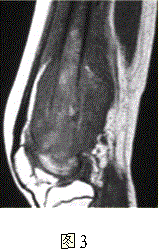

问题 患者男,16岁,左大腿下部疼痛伴肿胀2个月,逐渐加重。自感左膝上方胀痛,尤以夜间为著,伴行走困难。既往史及家族史无特殊。查体:左大腿下部明显肿胀,皮温较对侧升高。碱性磷酸酶明显增高。股骨平片及MRI见下图。 应该首先考虑的诊断为

选项 A.急性化脓性骨髓炎 B.骨结核 C.骨肉瘤 D.畸形性骨炎 E.骨转移瘤 F.软骨肉瘤

答案 C